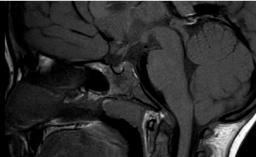

IRM de l’hypophyse normale ou presque : artefacts, kystes de la poche de Rathke – Claire Ancelet

Ce syndrome rare est caractérisé par une hypophyse postérieure absente ou ectopique, une tige interrompue et une hypoplasie hypophysaire antérieure…

Ce n’est pas le premier article sur le sujet, mais il est utile pour la pratique en ajoutant des données. Les auteurs rapportent les résultats de l’IRM cérébrale chez 192 enfants mesurant…